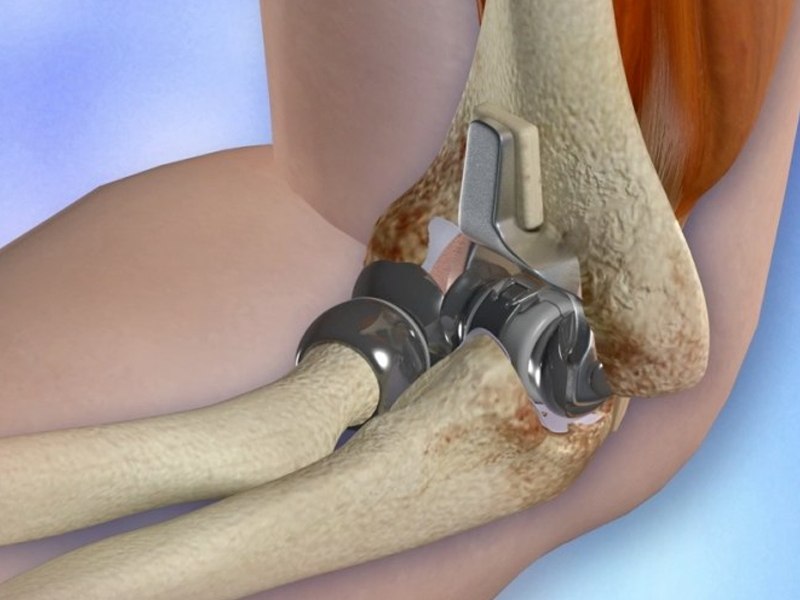

Total Elbow Replacement

Total Elbow Replacement (TER) is an advanced orthopedic surgical procedure performed to relieve severe elbow pain and restore movement in patients with damaged elbow joints. In this procedure, the damaged parts of the elbow joint are replaced with high-quality artificial implants, allowing smooth and painless joint movement.